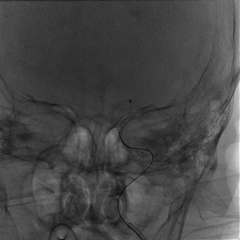

NeuroHawk Case 2